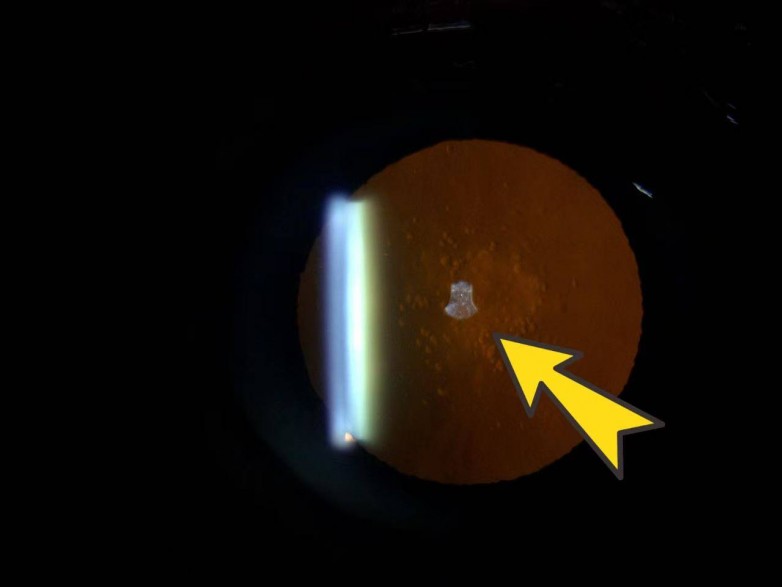

张女士右眼晶状体存在混浊

晶状体后囊下混浊且位于视线中央,早期白内障视力已受影响,尤其白天强光下更明显